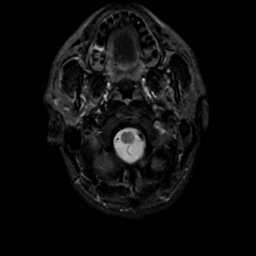

MR Study #8, March 31, 1991 -- Slice #2

[Home][Help][Clinical][Tour 1][Tour 2] Slice 2